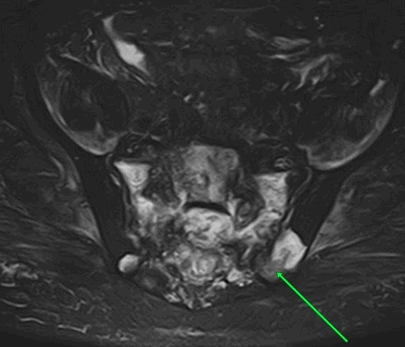

На рисунке – в обеих подвздошных костях и крестце имеются зоны повышенной интенсивности МР-сигнала по Т2-Stir

На рисунке – левосторонняя сакрализация L5 позвонка с формированием неоартроза и признаками воспаления в нем

Вторичное метастатическое поражение подвздошных костей и крестца

На рисунке - определяются очаги патологической инфильтрации в крестце и подвздошных костях